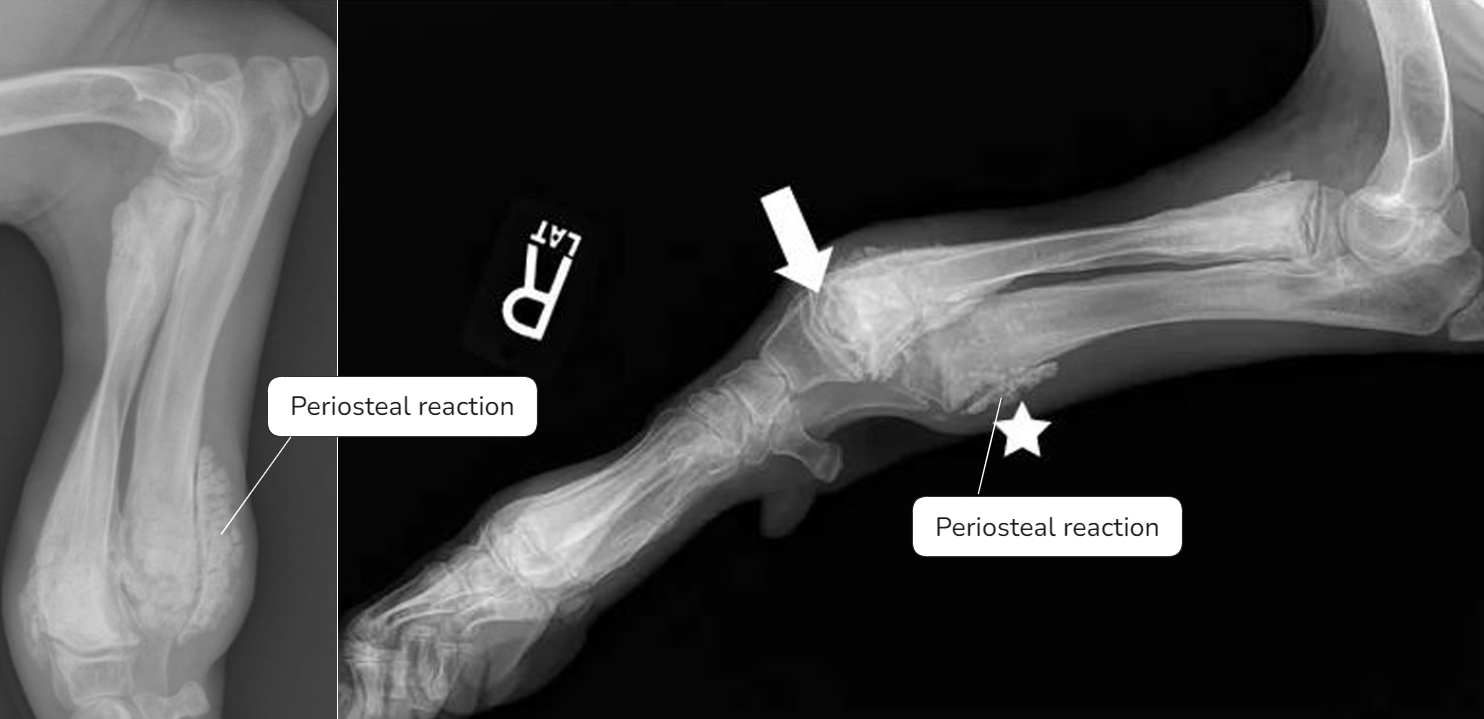

| - ์๋์ชฝ๋ง ์์์ผ๋ก ์ปค์ง๋ฉด์ flaring ์์์ ๋ณด์. | Early sign - Metaphyseal soft tissue swelling | ๋น์ ์์ ์ธ periosteal reaction์ด ์ฌํ๊ฒ ๋ํ๋จ, ์ฑ์ฅํ๋ ์์ ๋ฐ์ |